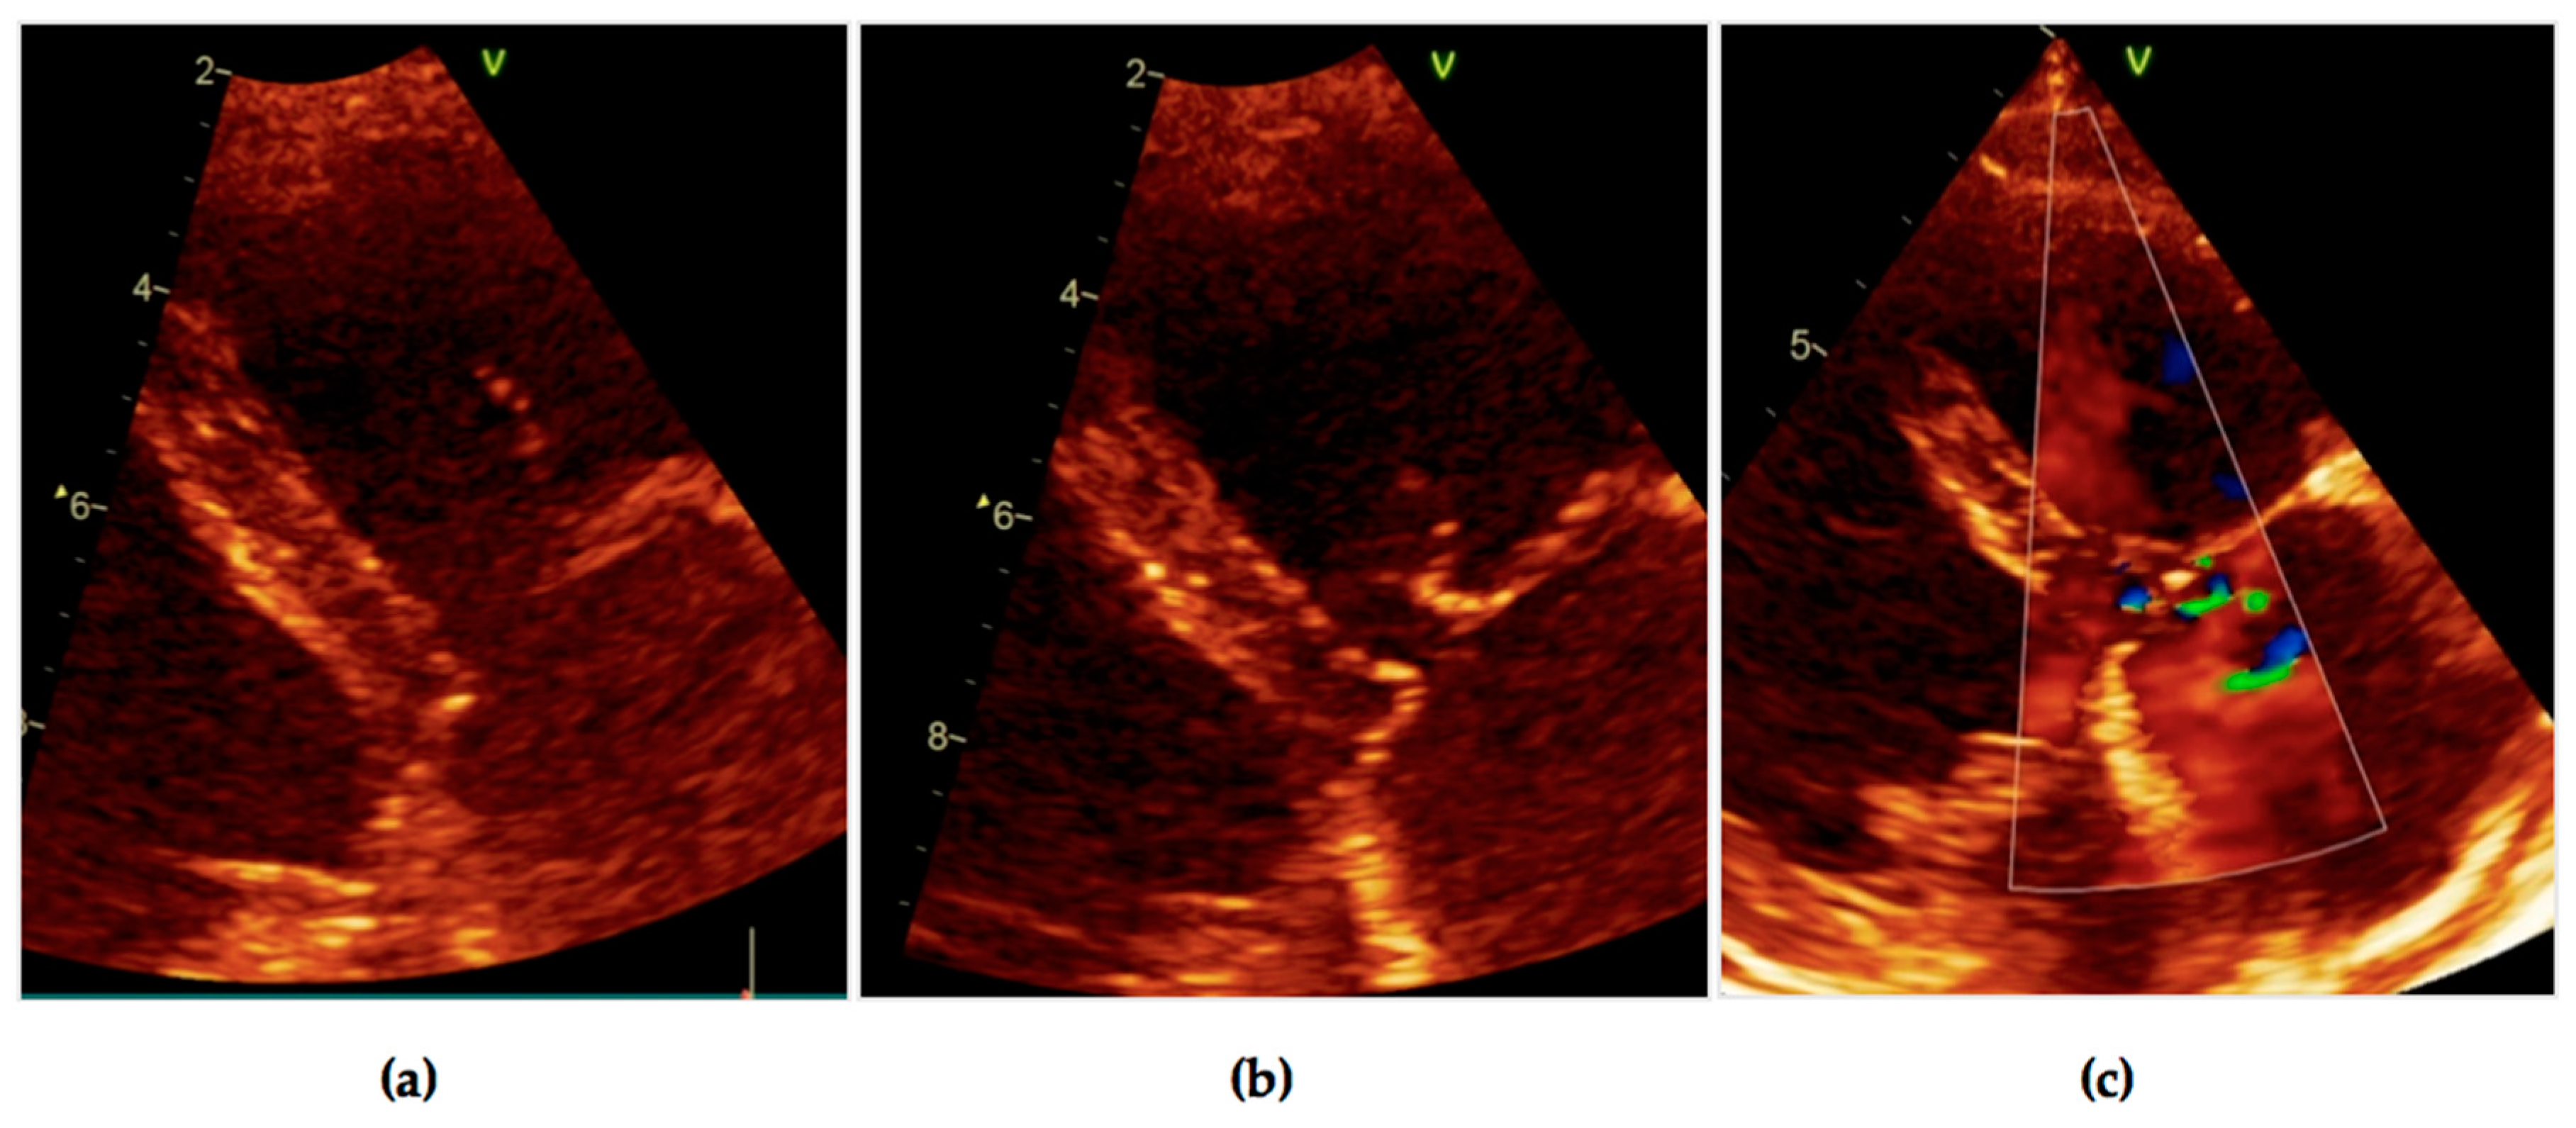

2. Case Report